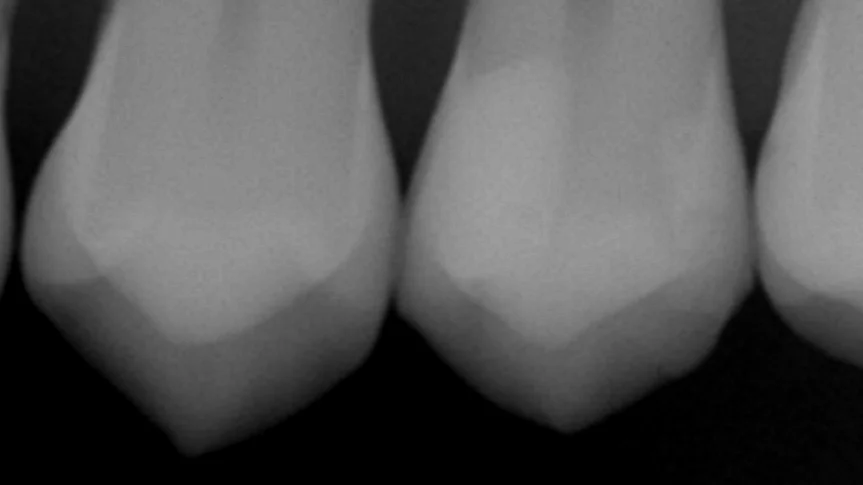

ちなみに、こちらの患者さん、実は画面上の右から2番目の歯も当院にて治療させていただいております。

それが1年ちょっと前なんですが、ブログでも書かせていただきました。

この時に詰めた歯のレントゲンがこちらですね。

画面右側の歯がそれになります。

1年程度では一才の段差がない状態をキープできていますね。

内面にもCは特に発生しておらず、状態としては非常に良好であると考えられます。